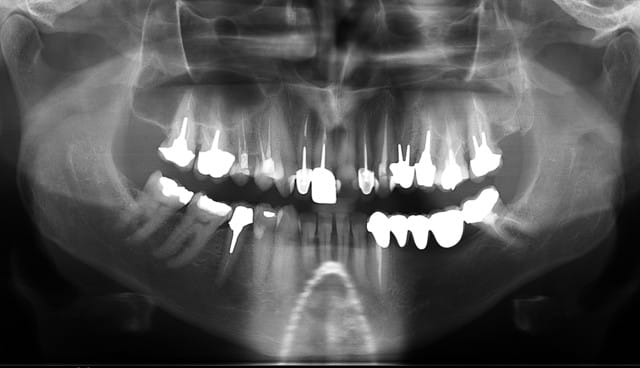

panoramique et photo pas de suite post op pas d'hematome, pas de douleur YESSSS

implants dans 5 mois si tvb

bridge de fou (33-37) qui est tombé il y a une semaine.

si possible 3 implants et le patient est ok pour expansion, reste plus qu'à voir pour le planing...

C'est pas le bridge qui est fou...

c'est les 12 endos au maxillaire !

WOW, jamais vu tant d'endo sur une arcade en 17 ans !

tu as quoi comme hauteur en 34/35/36 par rapport au V3?

j'ai pris les mesures, ça va etre "sportif" V3 "present", os D1, pas de hauteur je prendrais un cognac apres le kirr au petit dej.